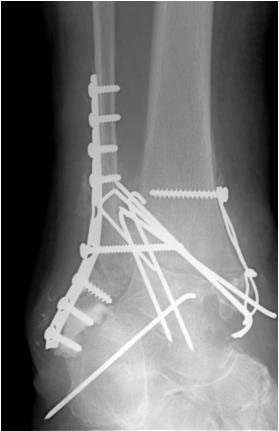

• Primäre oder posttraumatische Arthrose des OSG und USG (Abbildung 1, Abbildung 2).

• Revision einer gescheiterten Fusion des OSG/ USG (Abbildung 3, Abbildung 4).

• Pseudarthrosen (Abbildung 5, Abbildung 6).

Implantation des Nagels und BV-Kontrolle (Video 5). Schließlich erfolgt die Verriegelung des Nagels über entsprechende Zielvorrichtungen. Bei einigen Nageltypen gibt es nageleigene Kompressionsmechanismen, die eine zusätzliche Drucksteigerung im Bereich der Arthrodeseflächen des ehemaligen oberen und unteren Sprunggelenkes erlauben (Video 6). Die abschließende BV-Kontrolle in beiden Ebenen sollte eine regelrechte Stellung der Arthrodese mit 90° - Stellung im Rückfuß, in der anderen Ebene mit einem Rückfußvalgus von ungefähr 5° zeigen.